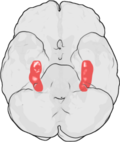

Locus ceruleus

- See also: Neurohistology#Locus_ceruleus.

- Blue dots - anterior to 4th ventricle in the pons.

Images: